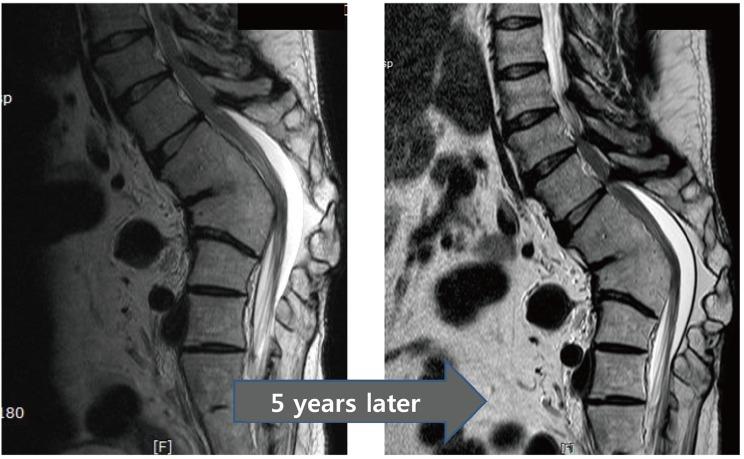

Ossification of the ligamentum flavum is a rare cause of thoracic myelopathy. It develops in East Asians more frequently than in people from other areas. The exact pathophysiology has not been elucidated yet; however, it largely depends on biomechanical alterations, especially changes in the tensile force. Because the spinal cord is compressed from the posterior side, the first and most common clinical manifestation is usually loss of functional gait and spastic paralysis, which develop as the spinal cord compression progresses. The choice of diagnostic imaging is T2 sagittal magnetic resonance imaging scanning. Whole spine scanning is mandatory to identify multiple areas of compression and any associated distal lumbar diseases. Fine computed tomography imaging is necessary to make a differential diagnosis and set up a precise surgical plan. Conservative treatment does not work in this disorder. Decompression surgery is the only option and prognosis after surgical treatment is better with this disorder than with other causes of thoracic myelopathy. The severity of preoperative symptoms and the time interval before surgical treatment are the most important prognostic factors.

黄韧带骨化是胸段脊髓病的罕见病因。东亚地区的发病率高于其他地区。确切的病理生理学尚未阐明;然而,其很大程度上取决于生物力学改变,尤其是张力变化。由于脊髓从后侧受到压迫,最初且最常见的临床表现通常是功能性步态丧失和痉挛性瘫痪,随着脊髓压迫的进展而出现。诊断性影像学检查选择T2矢状面磁共振成像扫描。必须进行全脊柱扫描以识别多个压迫部位以及任何相关的远端腰椎疾病。精细的计算机断层扫描成像对于进行鉴别诊断和制定精确的手术方案是必要的。保守治疗对这种疾病无效。减压手术是唯一的选择,并且与其他胸段脊髓病病因相比,这种疾病手术治疗后的预后更好。术前症状的严重程度和手术治疗前的时间间隔是最重要的预后因素。